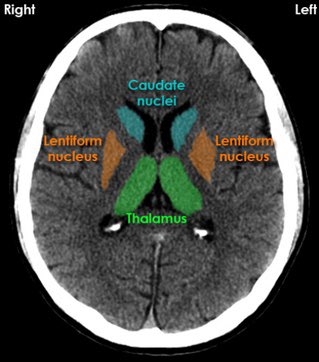

▫️Extra edge ➡️ DWI 🌟🧠

✳️Diffusion restriction involving the entire right caudate nucleus and right lentiform nucleus, cortex of the anterior right temporal lobe and right parietal lobe

🛑DWI can detect stroke as early as 45 min after the onset of the occlusion